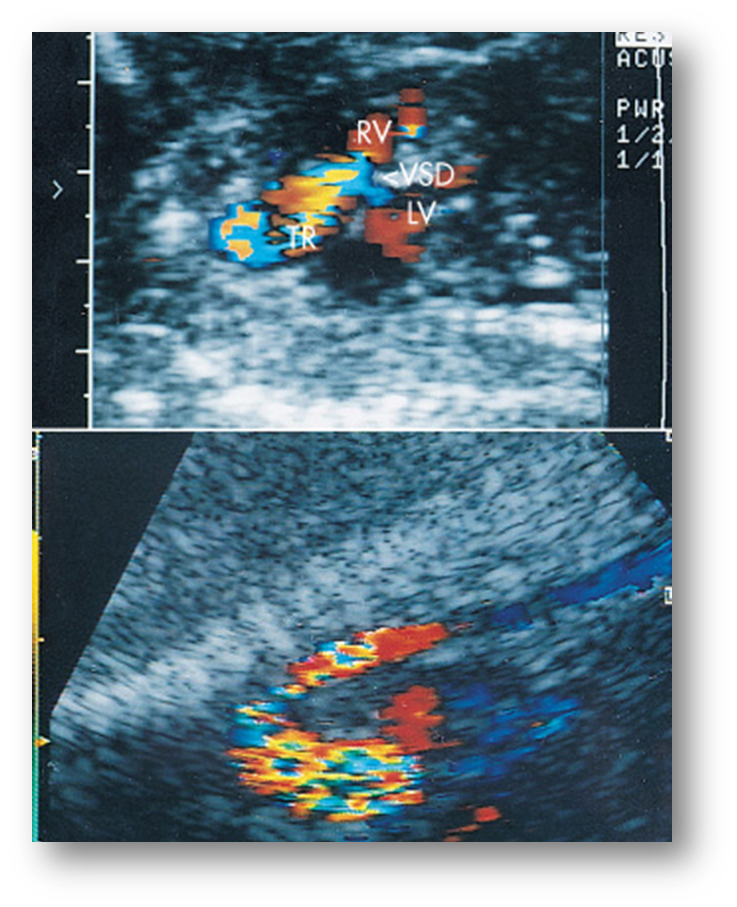

VSD

A VSD